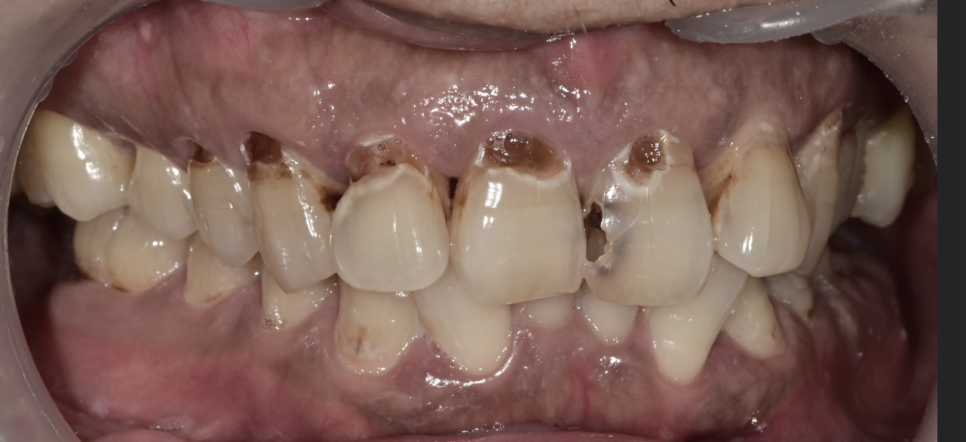

치과를 너무 오랜 기간 동안 못 오시다가 용기를 내어서 방문해 주셨습니다.

과거에 치료를 받으면서 턱이 너무 불편했던 기억으로 인해 치과 방문이 꺼려지셨다고 하셨습니다.

상실된 어금니 부위는 임플란트가 필요하고 해당 부위

말고도 앞니 쪽으로 다발성 우식이 생긴 상태고, 부위에 따라서 신경치료의 가능성이 큰 치아들도 보입니다.